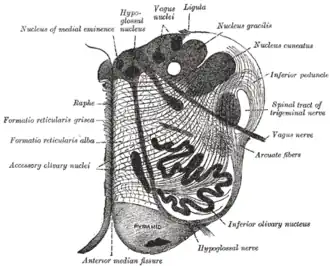

Section of the medulla oblongata at about the middle of the olive

Section of the medulla oblongata at about the middle of the olive -

The vagus nerve includes axons which emerge from or converge onto four nuclei of the medulla:

- The dorsal nucleus of vagus nerve – sends parasympathetic output to the viscera, especially the intestines

- The nucleus ambiguus – gives rise to the branchial efferent motor fibers of the vagus nerve and preganglionic parasympathetic neurons that innervate the heart

- The solitary nucleus – receives afferent taste information and primary afferents from visceral organs

- The spinal trigeminal nucleus – receives information about deep/crude touch, pain, and temperature of the outer ear, the dura of the posterior cranial fossa and the mucosa of the larynx